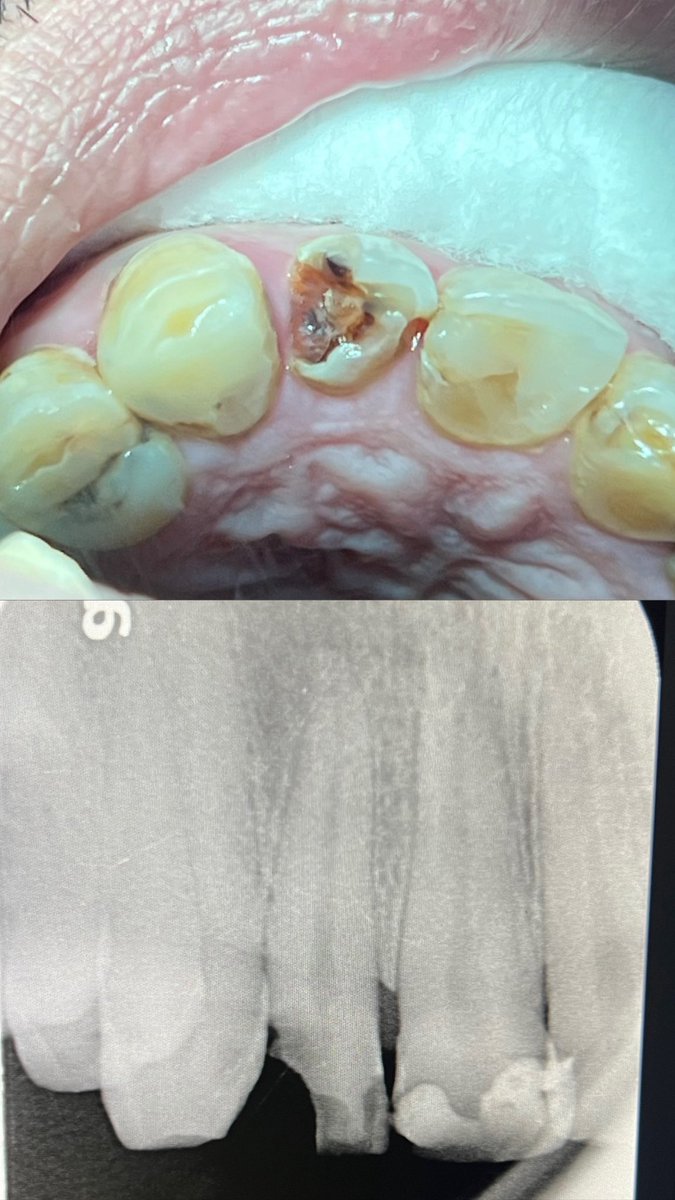

حالة جميلة لصباح اليوم 🙏🏻

Root Canal Treatment #34

Dx:SIP+SAP

Gingival overgrowth and deep caries in the distal wall, Rebuild the distal wall to achieve optimum isolation ✨

Next Step: Crown

#Endodontics